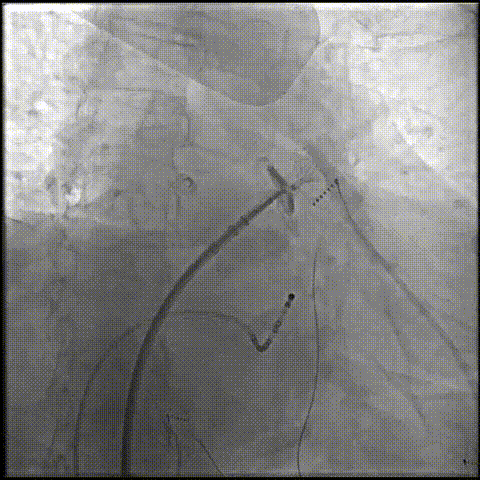

左心耳造影及测量:RAO30,CAUD20测量锚定区22.79mm,开口区31.68mm。

左心耳造影及测量

ICE下测量锚定区22.31mm,开口区28.73mm,选择LAMax 2436 Plus型号封堵器。

锚定伞锚定在主干区域,再将封堵盘逐渐打开,保证封堵效果,封堵盘完全打开后造影,外盘覆盖外口,封堵完全,无残余分流。

锚定伞打开

封堵盘打开